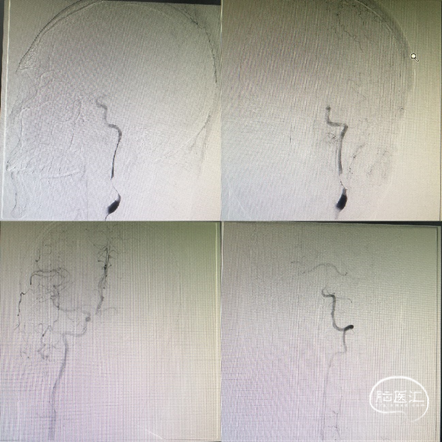

造影发现:左侧颈内动脉C1段重度狭窄,终末端闭塞;右侧前循环及后循环向左侧前循环代偿差。

6F NeuronMax长鞘引至左颈总动脉末端,保护伞下,3mm×20mm球囊扩张C1狭窄处。

在球囊支撑下将6F NeuronMax越过C1段狭窄,回收保护伞,造影发现MCA上干闭塞。

造影提示左侧颈内动脉系统再通,C1段狭窄处支架成型良好。